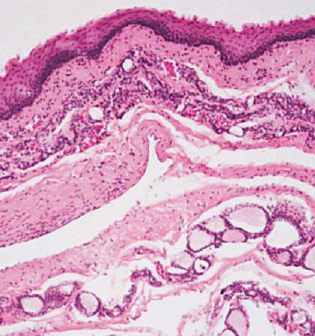

| Pilar (Trichilemmal) cysts 毛髮囊腫 |

- | 頭皮 (90%)、多發性(70%) | - | 無凹陷開口 |

cholesterol clefts(90%), 淡染, 無 granular layer |

||||

| 破裂 → 發炎細胞湧入 cyst → secondary inflammation | ||||

| Dermoid Cyst | Teratoma | 口底中線 | 兒童、年輕 | 多個 germ layer |

正角化上皮, Cyst Wall 有皮膚附屬物(皮脂腺細胞核居中) |